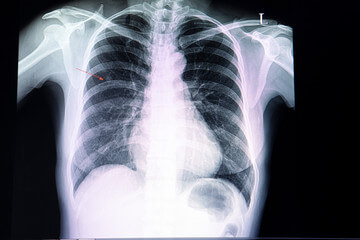

폐결절은 폐에 형성되는 작은 덩어리 또는 종양을 의미합니다. 이러한 결절은 폐의 X선이나 기타 영상 검사를 통해 발견될 수 있으며 다양한 원인에 의해 발생할 수 있습니다. 폐결절은 종종 미립자, 감염, 염증, 혹은 기타 조직의 비정상적인 성장으로 인해 형성될 수 있습니다.

흉부 X선 검사

폐결절은 보통 흉부 X선으로 처음 발견될 수 있습니다. X선은 폐결절의 크기와 일반적인 특징을 파악하는 데 도움이 될 수 있습니다. 그러나 X선은 폐결절의 세부적인 특성을 파악하기에는 제한적일 수 있습니다.

흉부 전산화단층촬영(CT)

CT 스캔은 폐결절을 더 자세히 평가하는 데 사용됩니다. CT는 폐결절의 크기, 형태, 밀도, 혈관의 관계 등을 상세하게 보여줄 수 있습니다. 또한 3D 재구성을 통해 폐결절의 위치와 주변 구조를 더 잘 확인할 수 있습니다.